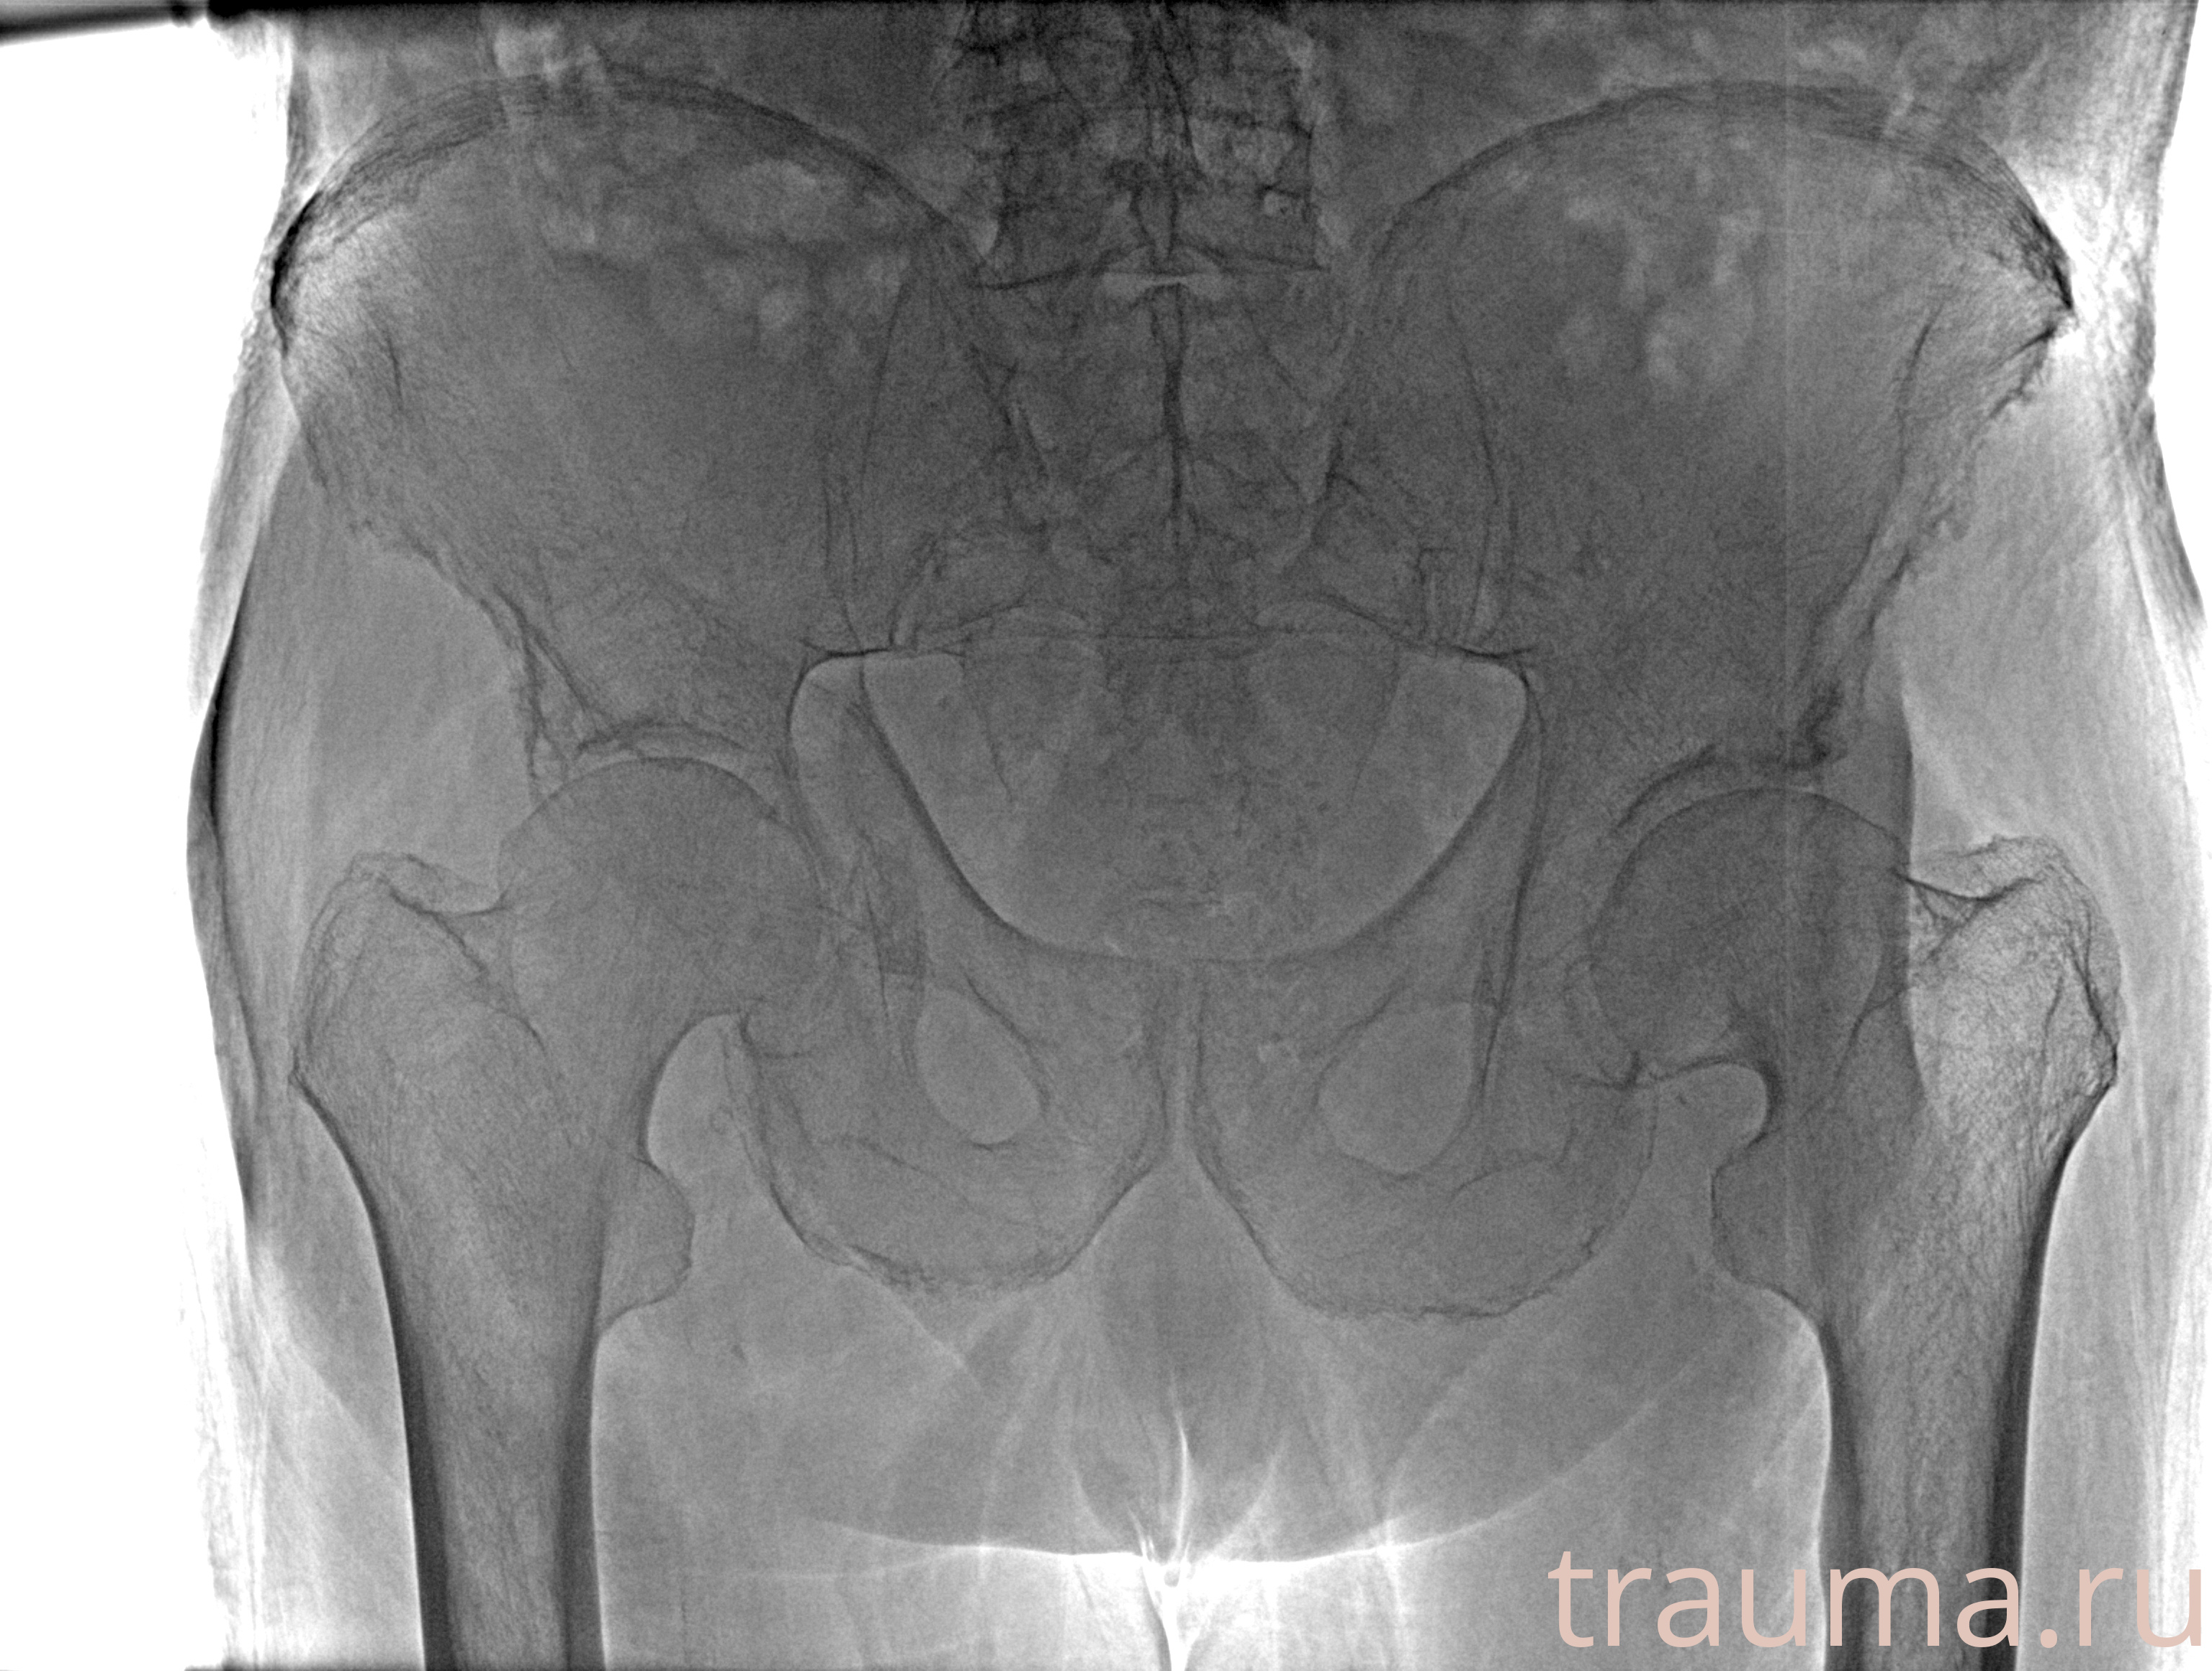

Рентгенограммы

Рентген на дому: по вашему адресу приезжает врач-рентгенолог, травматолог-ортопед с мобильным рентгеновским аппаратом, проводит диагностику травмы или заболевания, делает необходимые рентгенограммы, дает рекомендации по дальнейшему лечению. Получить качественные снимки в домашних условиях возможно благодаря уникальной методике, разработанной МосРентген Центром для института  Склифосовского